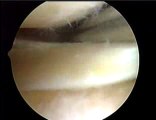

1 - INSTABILITE DE L’EPAULE CHEZ LE SPORTIF

Evolution des techniques arthroscopiques, résultats

Luxations antérieures - Page 10 du document :